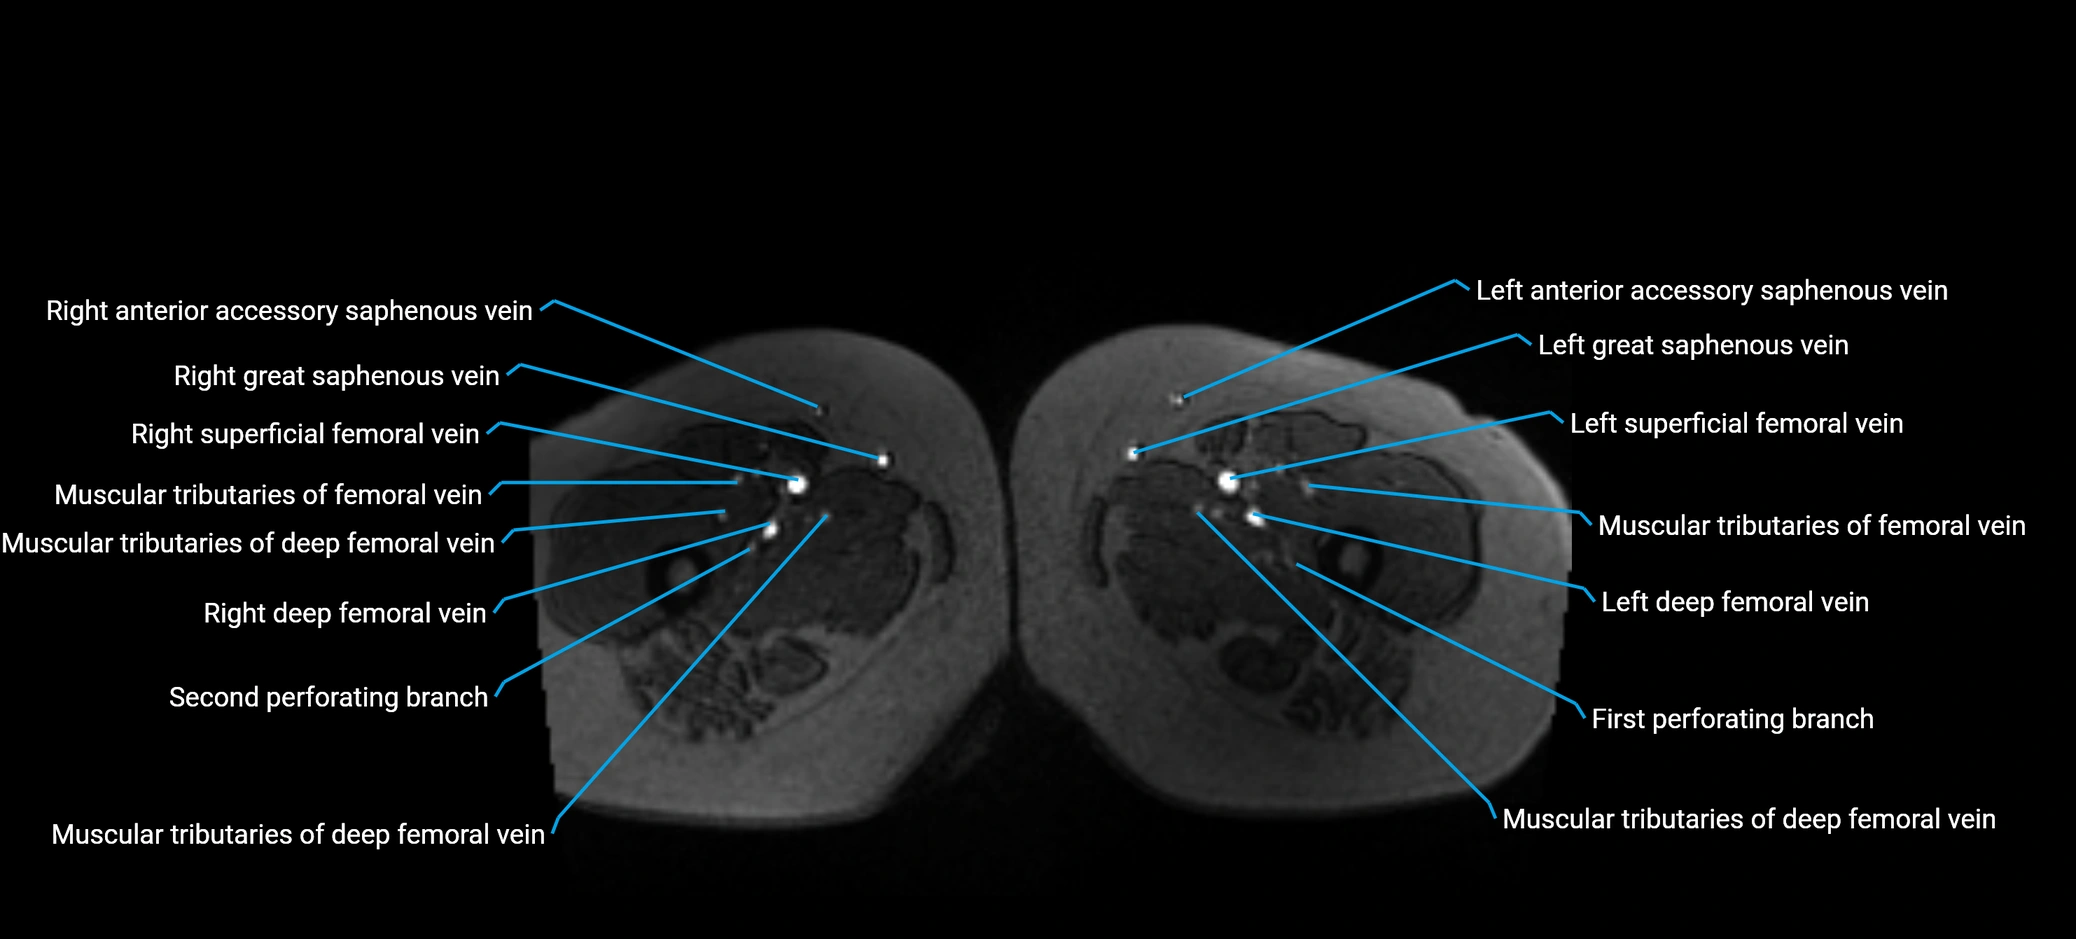

MRI image

image